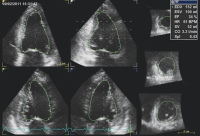

Echokardiographie aktuell: Basis- und erweiterte Evaluierung der systolischen Linksventrikelfunktion nach Myokardinfarkt

Journal für Kardiologie - Austrian Journal of Cardiology 2011; 18 (3-4): 102-104 Volltext (PDF) Abbildungen mit Filmsequenzen